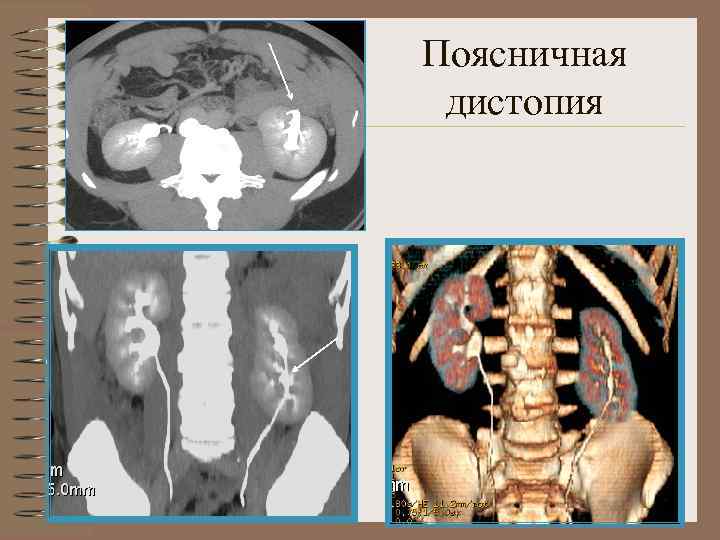

Поясничная дистопия • Почка расположена ниже обычного • Лоханка ориентирована латерально, по передней поверхности • Короткий мочеточник

Поясничная дистопия Поворот лоханкой кпереди

Поясничная дистопия